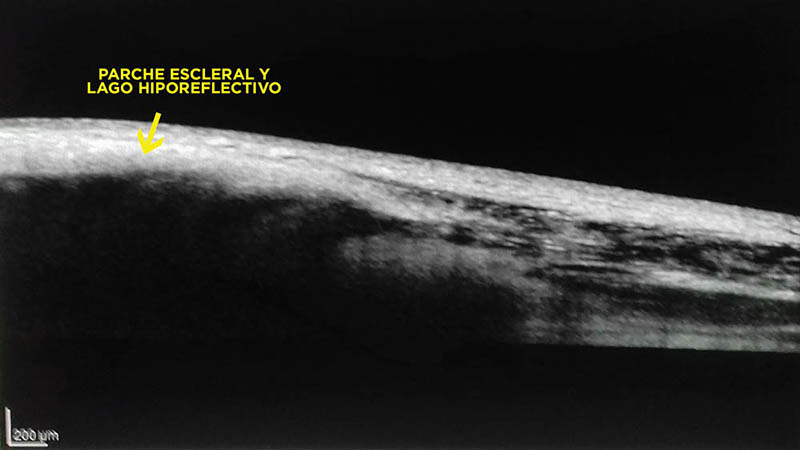

Figura 4:

Observación de la esclera en pacientes con hipotonía persistente aún con parche escleral. La esclera presenta desorganización de las lamelas de fibras de colágeno y áreas hiporreflectivas.

Figura 5:

Magnificación de la imagen de la figura 04.